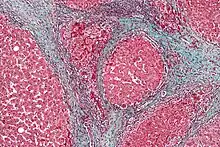

Liver histology is altered in HRS while kidney histology is normal. The upper image is a trichrome stain (chicken wire appearance) cirrhosis of the liver, the most common cause of HRS. The lower image is a PAS stain of normal kidney histology. | |